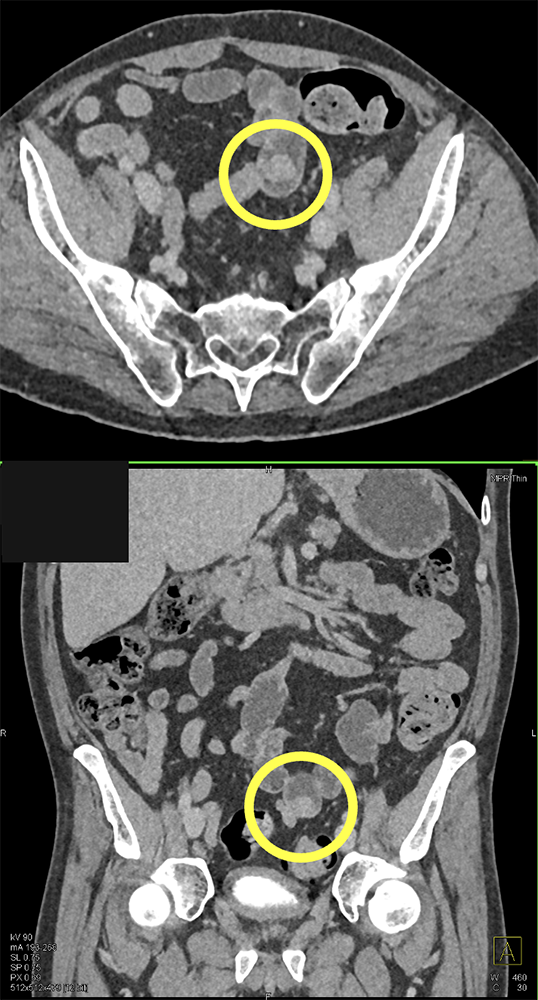

GI Bleed with Leiomyoma Ileum with Negative Capsule Study ![]() |

![]() |